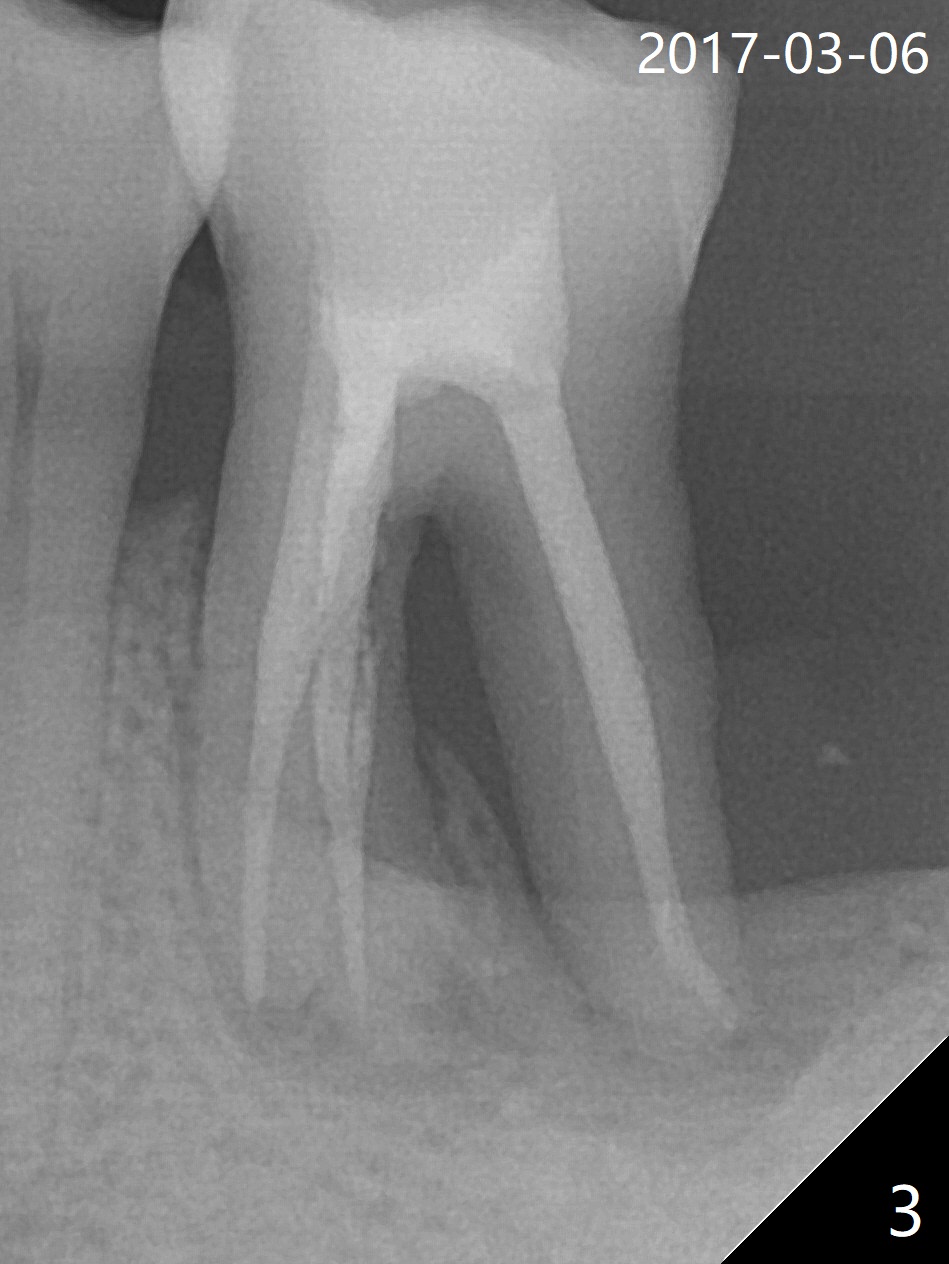

After tooth extraction (Fig.4), a medium-sized implant (4.5 mm, Fig.5 green) will be placed in the mesial socket, but the coronal end of the long axis of the implant (white line) will be in the middle of the socket for future restoration. The gingival margin of the socket is also uneven (Fig.6 pink). Before placement of the final abutment (Fig.7 blue), pack allograft (red circles) over the exposed implant surface until the platform of the implant. After placement of Osteogen plug in the distal socket (Fig.8 yellow), more of allograft is placed coronally. An immediate provisional (Fig.9 white) is to be fabricated to keep the graft in place. If the socket is deemed to be unsuitable for immediate implant, place PRF membrane(s) distoocclusally (Fig.10 purple), followed by collagen membrane and suturing.